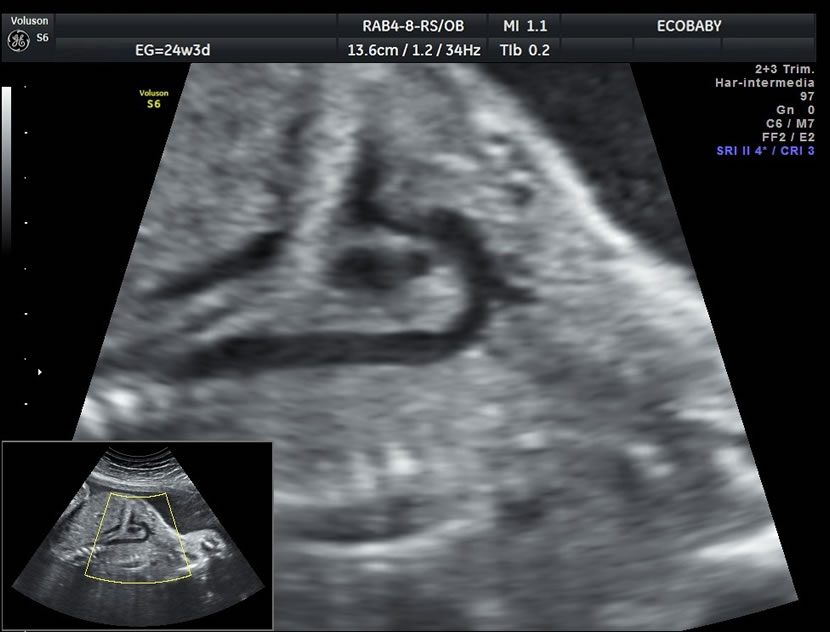

Cerebro, cuello, cara, tórax, corazón (diferentes cortes que muestran las cavidades y la correcta entrada y salida de arterias y venas), abdomen (normalidad de la pared, estómago, intestino, riñones, vejiga), miembros inferiores y superiores y columna vertebral.